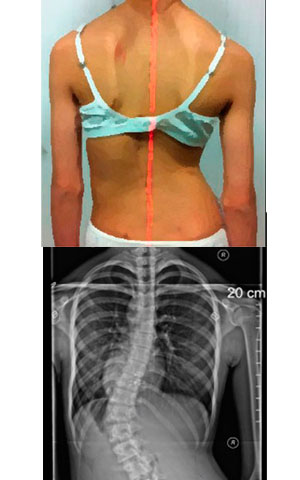

Despistaje de Escoliosis: que buscar

¿Qué es lo que buscan?

Hay ciertas cosas que pueden detectarse:

• Un hombro más alto que otro

• Un omoplato (escápula) más prominente que el otro

• Una cadera más alta que la otra

• Una pierna parece más larga

• El tronco y la parrilla costal están desplazados hacia un lado

• La cabeza no está centrada sobre la pelvis

• Asimetría de la cintura

• La ropa cuelga de manera asimétrica y cuando el/la niño/ niña se inclinan hacia delante por la cintura, un lado parece más alto

Algunos de estos signos de escoliosis pueden ser difíciles de detectar, especialmente para el observador no entrenado.

TEST DE ADAMS

• El examinador solicita al paciente que se incline hacia adelante con los brazos flojos y las rodilla extendidas.

• Se observan los hemitórax (que deben ser simétricos).

• Si existe una asimetría a nivel torácico o lumbar, se dice que la maniobra de Adams es positiva y se debe descartar una escoliosis solicitándole radiografía

La Escoliosis produce la formación de una giba torácica (prominencia de los arcos costales en un lado del tórax) y una giba lumbar (por el deslizamiento de los músculos que están encima de estas vertebras).